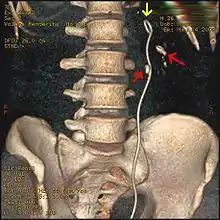

Three-dimensional reconstructed CT scan image of a ureteral stent in the left kidney (indicated by yellow arrow), with a kidney stone in the inferior renal pelvis (highest red arrow) and one in the ureter beside the stent (lower red arrow)

Ureteroscopic surgery

Ureteroscopy has become increasingly popular as flexible and rigid fiberoptic ureteroscopes have become smaller. One ureteroscopic technique involves the placement of a ureteral stent (a small tube extending from the bladder, up the ureter and into the kidney) to provide immediate relief of an obstructed kidney. Stent placement can be useful for saving a kidney at risk for postrenal acute kidney failure due to the increased hydrostatic pressure, swelling and infection (pyelonephritis and pyonephrosis) caused by an obstructing stone. Ureteral stents vary in length from 24 to 30 cm (9.4 to 11.8 in) and most have a shape commonly referred to as a "double-J" or "double pigtail", because of the curl at both ends. They are designed to allow urine to flow past an obstruction in the ureter. They may be retained in the ureter for days to weeks as infections resolve and as stones are dissolved or fragmented by ESWL or by some other treatment. The stents dilate the ureters, which can facilitate instrumentation, and they also provide a clear landmark to aid in the visualization of the ureters and any associated stones on radiographic examinations. The presence of indwelling ureteral stents may cause minimal to moderate discomfort, frequency or urgency incontinence, and infection, which in general resolves on removal. Most ureteral stents can be removed cystoscopically during an office visit under topical anesthesia after resolution of urolithiasis.[114] Research is currently uncertain if placing a temporary stent during ureteroscopy leads to different outcomes than not placing a stent in terms of number of hospital visits for post operative problems, short or long term pain, need for narcotic pain medication, risk of UTI, need for a repeat procedure or narrowing of the ureter from scarring.[115]